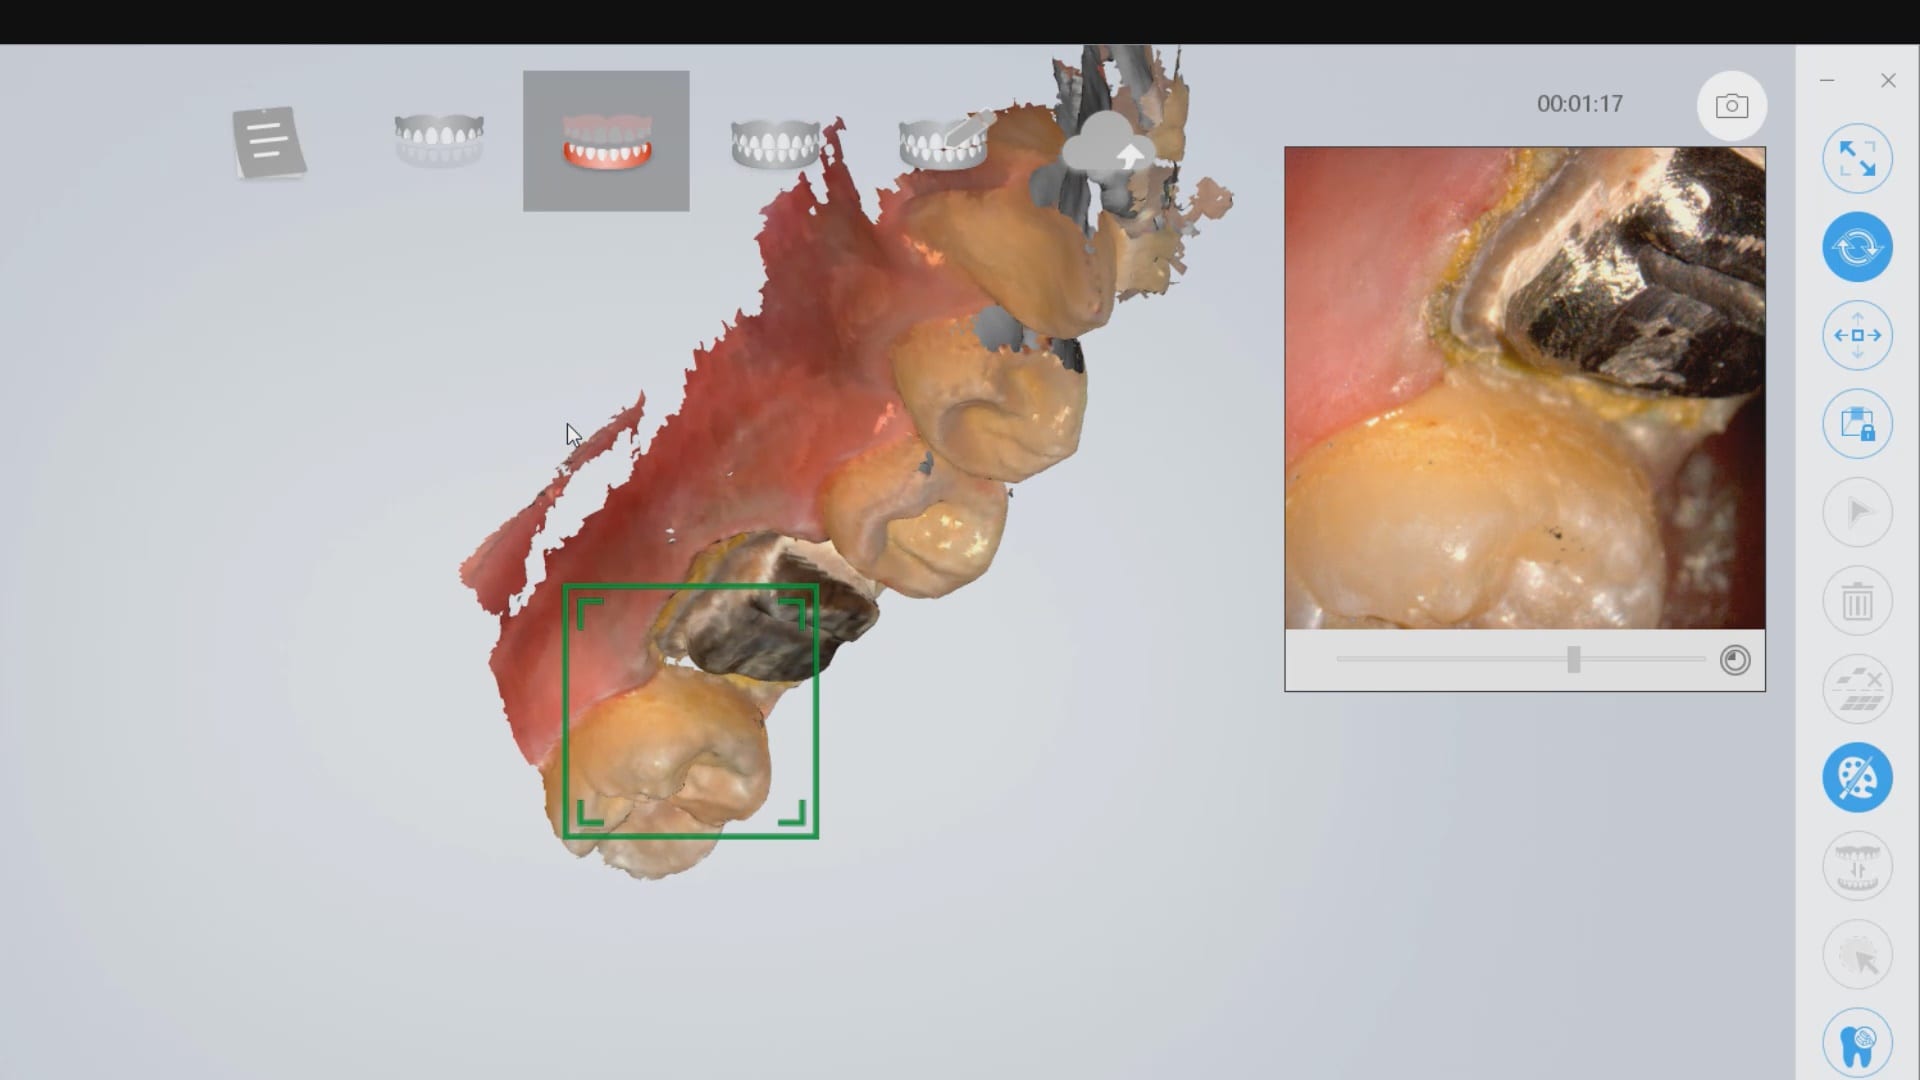

Lower First Molar Deep Margins Scanned by Shining AoralScan

In this video we demonstrate how the Aoralscan from Shinning 3D captures deep margins.

This video is deliberately captured slowly so a new user can appreciate how to hold the camera to capture the margins and the contacts of the adjacent teeth. You also have the opportunity to place your own margins and the path of draw before submit the case to the lab.